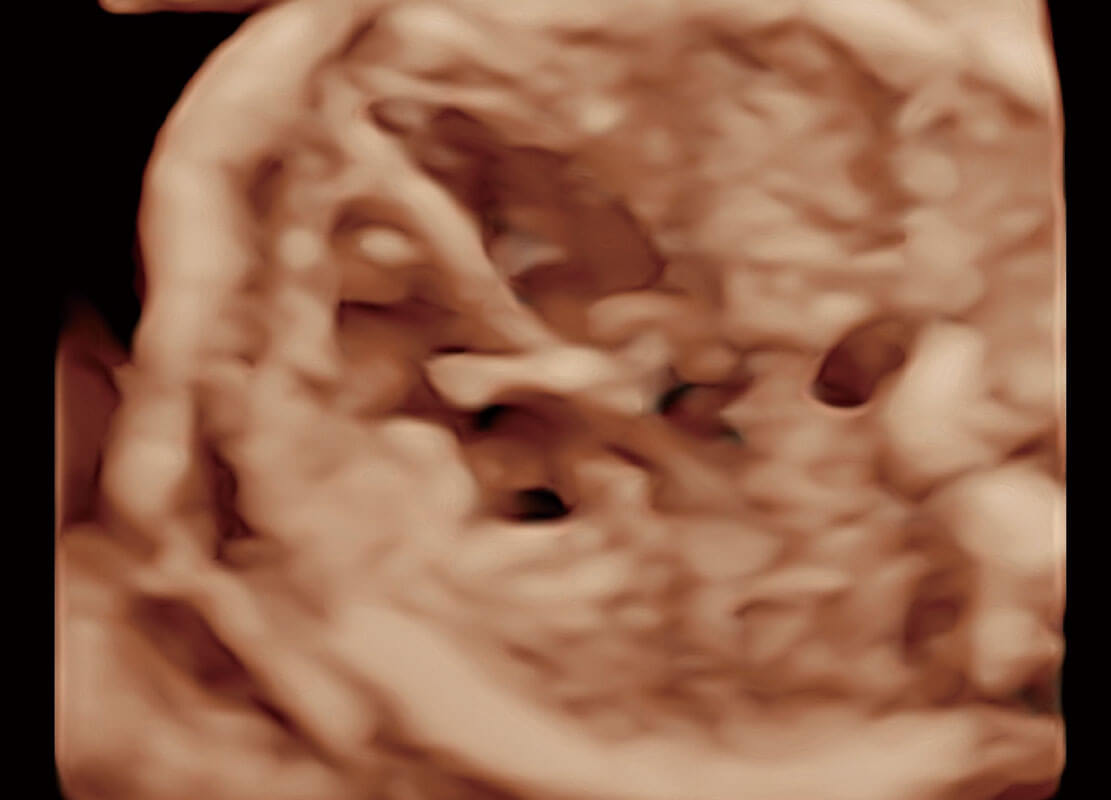

腔内三维-光影成像

高分辨率容积成像-早孕胎儿